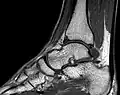

MRT des Sprunggelenks in T1-Wichtung -

- Protonendichte-gewichtete (PDw) Bilder sind flau (weniger Gewebekontrast), aber scharf. Knorpel kann sehr detailliert beurteilt werden. In Verbindung mit einem Fettsättigungsimpuls gehören PDw-Bilder deshalb zum Standard in Gelenkuntersuchungen.